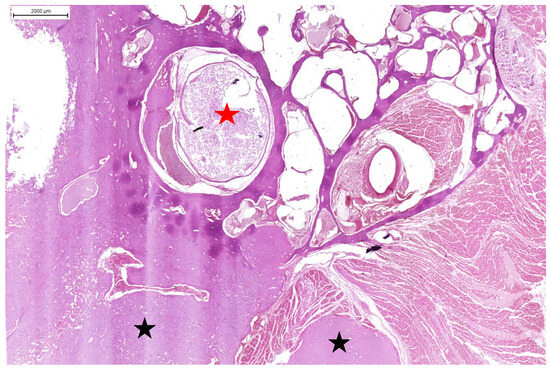

3.3. Results of Microscopic Examination